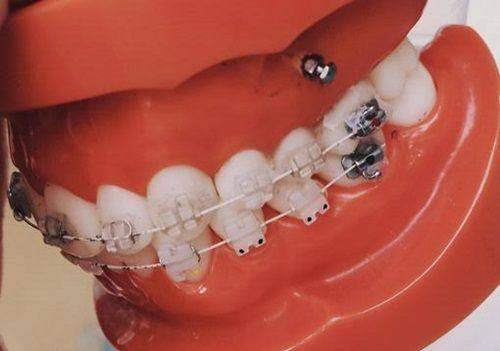

上海摩尔松江口腔医院拥有一支专精的医疗团队,他们不仅具备扎实的专精知识,还拥有丰富的临床经验。医生们会根据每位患者的具体情况,制定个性化的治疗方案。无论是补牙、拔牙、洗牙,还是正畸、种植牙等复杂的口腔手术,他们都能游刃有余地完成。而且,医院还定期邀请国内外有名的口腔骨干医生进行学术交流和指导,不断提升团队的医疗水平。

上海摩尔松江口腔医院采用精良的口腔诊疗设备,如数字化口腔全景机、口腔显微镜等,能够精细地诊断口腔问题。在治疗过程中,医院严格遵循无菌操作原则,确保患者的安心。同时,医院还注重患者的体验,提供舒适的就诊环境和贴心的服务。从预约挂号到治疗结束,每一个环节都有专人引导和服务,让患者感受到家一般的温暖。